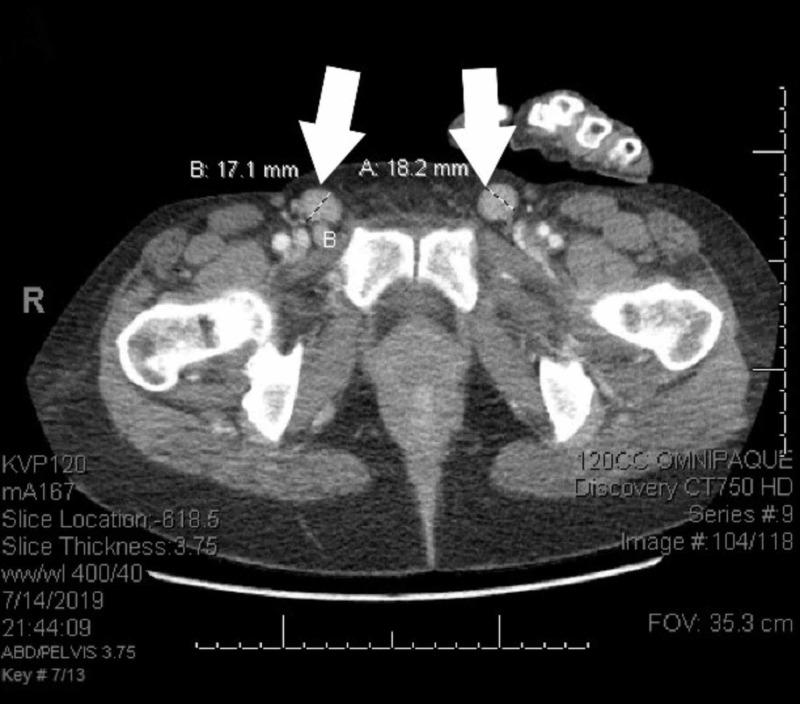

Plasmablastic lymphoma (PBL) is a rare form of non-Hodgkin lymphoma that is highly aggressive and carries a poor prognosis. Although the standard chemotherapy choice for most diffuse large B-cell lymphomas (DLBCL) is R-CHOP (rituximab, cyclophosphamide, doxorubicin, vincristine, and prednisone), subtypes of DLBCL such as PBL are less responsive to this treatment regimen. The preferred regimens for PBL include infusional EPOCH (etoposide, prednisone, vincristine, cyclophosphamide, and doxorubicin hydrochloride), HyperCVAD (cyclophosphamide, vincristine sulfate, doxorubicin hydrochloride, and dexamethasone), or CODOX-M/IVAC (cyclophosphamide, vincristine, doxorubicin, high-dose methotrexate/ifosfamide, etoposide, and high-dose cytarabine). Recent studies have begun to investigate the addition of other agents to these regimens to improve survival. This case report is about a patient with a history of advanced acquired immunodeficiency syndrome (AIDS) with a cluster of differentiation 4 (CD4) count <20 who had CD20 negative plasmablastic lymphoma and was successfully treated with the combination of bortezomib and dose-adjusted EPOCH (V-EPOCH) and intrathecal chemotherapy, achieving complete response with optimal tolerance. To our knowledge, this is the first case to demonstrate a complete response with V-EPOCH for PBL in advanced AIDS with CD4 <20. We aim to highlight the importance of standardizing effective chemotherapeutic approaches to this cancer entity and augment the effectiveness of V-EPOCH therapy in the literature review.